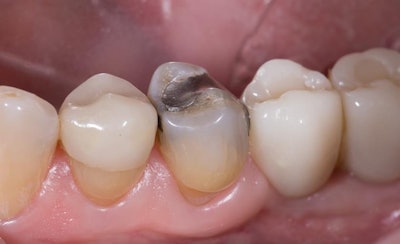

Once the failing amalgam was completely removed and the mesial caries excavated, Kuraray's Caries Detector was applied to assist in verification of complete caries removal. A composite buildup was placed using Clearfil Universal Bond Quick (Kuraray Noritake) and composite resin (figure 2, below).

Clearfil Universal Bond Quick is just as its name indicates: universal and quick. It was chosen for its ease of use without compromised strength. It was used for bonding of the composite buildup and again later for bonding of the Katana STML A3 crown (Kuraray Noritake) with Panavia SA Cement Universal (Kuraray Noritake) translucent cement.